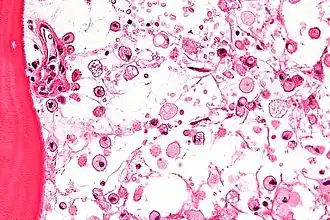

Las células que acumulan el glucocerebrósido son denominadas células de Gaucher, y adquieren un aspecto característico:[6] se muestran grandes, con aspecto mesenquimatoso, núcleo no desplazado y citoplasma con aspecto de "celofán arrugado". Las podemos ver sobre todo en médula ósea, hígado, bazo y ganglios linfáticos.[6]